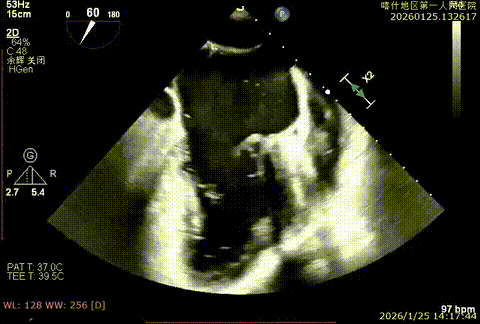

该例患者为VFMR,术前制定手术策略:患者二尖瓣重度反流,后叶严重栓系,心房心室扩大。患者瓣口面积4.5cm2,预计使用两枚XTR解决患者瓣叶脱垂和反流。考虑到先于2区进行钳夹,应该能获得足够的房间隔穿刺高度。术中经不断调整穿刺位点,最终穿刺高度4.4cm。成功穿刺后将第一枚XTR送入二尖瓣正上方,进行弹道测试Orientation调整后,最终定位于2区正上方下左心室。第一枚夹子在左室成功捕捞和钳夹瓣叶后,瓣叶反流程度显著降低,夹子外侧仍见部分反流,随后在第一枚夹子外侧再次放置一枚XTR,瓣叶反流程度进一步降低至微量。通过TEE观察,二尖瓣双孔组织桥稳定,跨瓣压差3mmHg,肺静脉逆流改善明显,手术安全结束。

X-plan重度反流